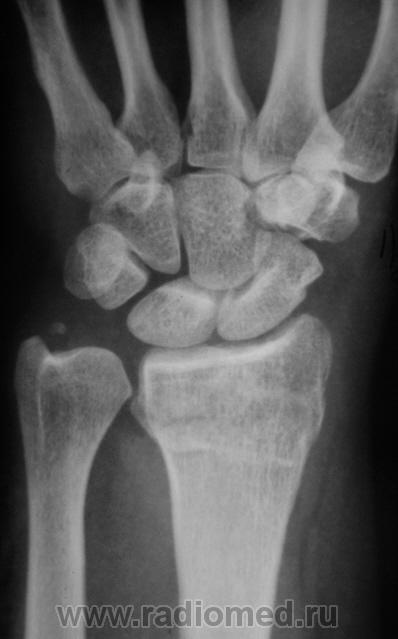

Пол пациента: Мужской пол Тип патологии: Травма Область исследования: Скелетно-мышечная система Методы исследования: Rg Травма. Пациент направлен врачом хирургом на рентгенографию лучезапястного сустава. Произведено исследование. Ваше мнение коллеги? Thu, 15/10/2009 - 21:47 #1 Наталия Offline Last seen: 8 years 8 months ago Joined: 30.07.2008 - 13:24 Posts: 538 Откол части шиловидного отростка локтевой кости, перелом лучевой кости в питичном месте, перелом ладьевидной кости. Может отрыв крючка. Thu, 15/10/2009 - 22:25 #2 v1tal Offline Last seen: 4 years 10 months ago Joined: 07.06.2008 - 19:41 Posts: 1779 Можно добавить краевой перелом кости-трапеции. "Знаешь, у некоторых врачей есть комплекс мессии — им необходимо спасать мир. А у тебя комплекс Рубика — тебе необходимо решать головоломки." Sun, 18/10/2009 - 23:33 #3 Катенёв Валенти... Offline Last seen: 7 years 1 month ago Joined: 22.03.2008 - 22:15 Posts: 54876 Так выходит - 3 перелома!? Mon, 19/10/2009 - 20:15 #4 Анатолий Владим... Offline Last seen: 7 years 11 months ago Joined: 16.10.2009 - 21:16 Posts: 1941 В ладьевидной кости в норме часто можно наблюдать ступеньку по наружному контуру, которая симулирует перелом. Для окончательного решения вопроса необходима рентгенограмма костей запястья в косой проекции.

Откол части шиловидного отростка локтевой кости, перелом лучевой кости в питичном месте, перелом ладьевидной кости. Может отрыв крючка.

Можно добавить краевой перелом кости-трапеции.

Так выходит - 3 перелома!?

В ладьевидной кости в норме часто можно наблюдать ступеньку по наружному контуру, которая симулирует перелом. Для окончательного решения вопроса необходима рентгенограмма костей запястья в косой проекции.